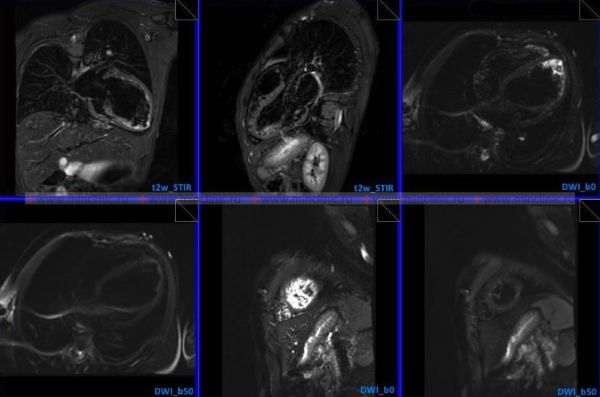

Некоторые виды МРТ (магнитно-резонансной томографии) органов грудной клетки требуют применения специального препарата — контраста. Контрастное вещество водится пациенту через вену локтевого сгиба или кисти. Контраст при МРТ (магнитно-резонансная томография) органов грудной клетки, накапливаясь в изменённых тканях, усиливает получаемое изображение. Это даёт наиболее подробную картину состояния исследуемого органа или ткани для врача рентгенолога, который будет делать описание полученных при МРТ изображений.

Внутривенный контраст с гадолинием — это неионное парамагнитное контрастное средство для магнитно-резонансной томографии. Парамагнитные свойства определяют контрастное усиление при выполнении МРТ 3,0 Т (тесла). Внутривенное введение препарата (контраста) вызывает усиление сигнала из участков тканей только тех органов, которые имеют дисфункцию в результате повреждения при каком-либо патологическим процессе. Это обеспечивает большую информативность от полученного изображений по сравнению с данными МРТ того же органа без применения контрастного усиления.

МРТ (магнитно-резонансной томографии) органов грудной клетки может показать следующие нарушения в сердце, лёгких или грудной клетке:

- патологические массы и опухоли в грудной полости;